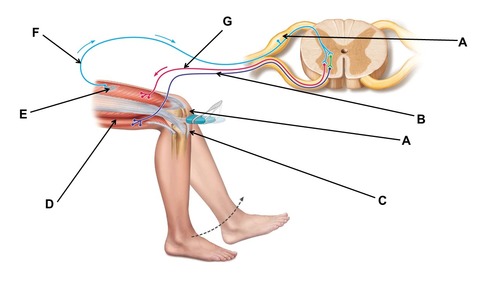

Name the region within bracket D.

This test could be used to test the functioning of which peripheral nerve?

femoral

When conducting this reflex, which muscle(s) are inhibited?

hamstrings

When conducting this reflex, which muscle(s) contracts?

quadriceps